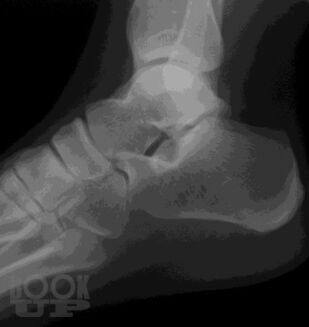

В учебном пособии представлены общие положения о развитии и анатомии опорно-двигательного аппарата, методы лучевой диагностики и показания для их использования при исследовании костей и суставов, изложены основы посиндромного подхода к диагностике заболеваний костно-суставной системы, основы диагностики травматических повреждений.